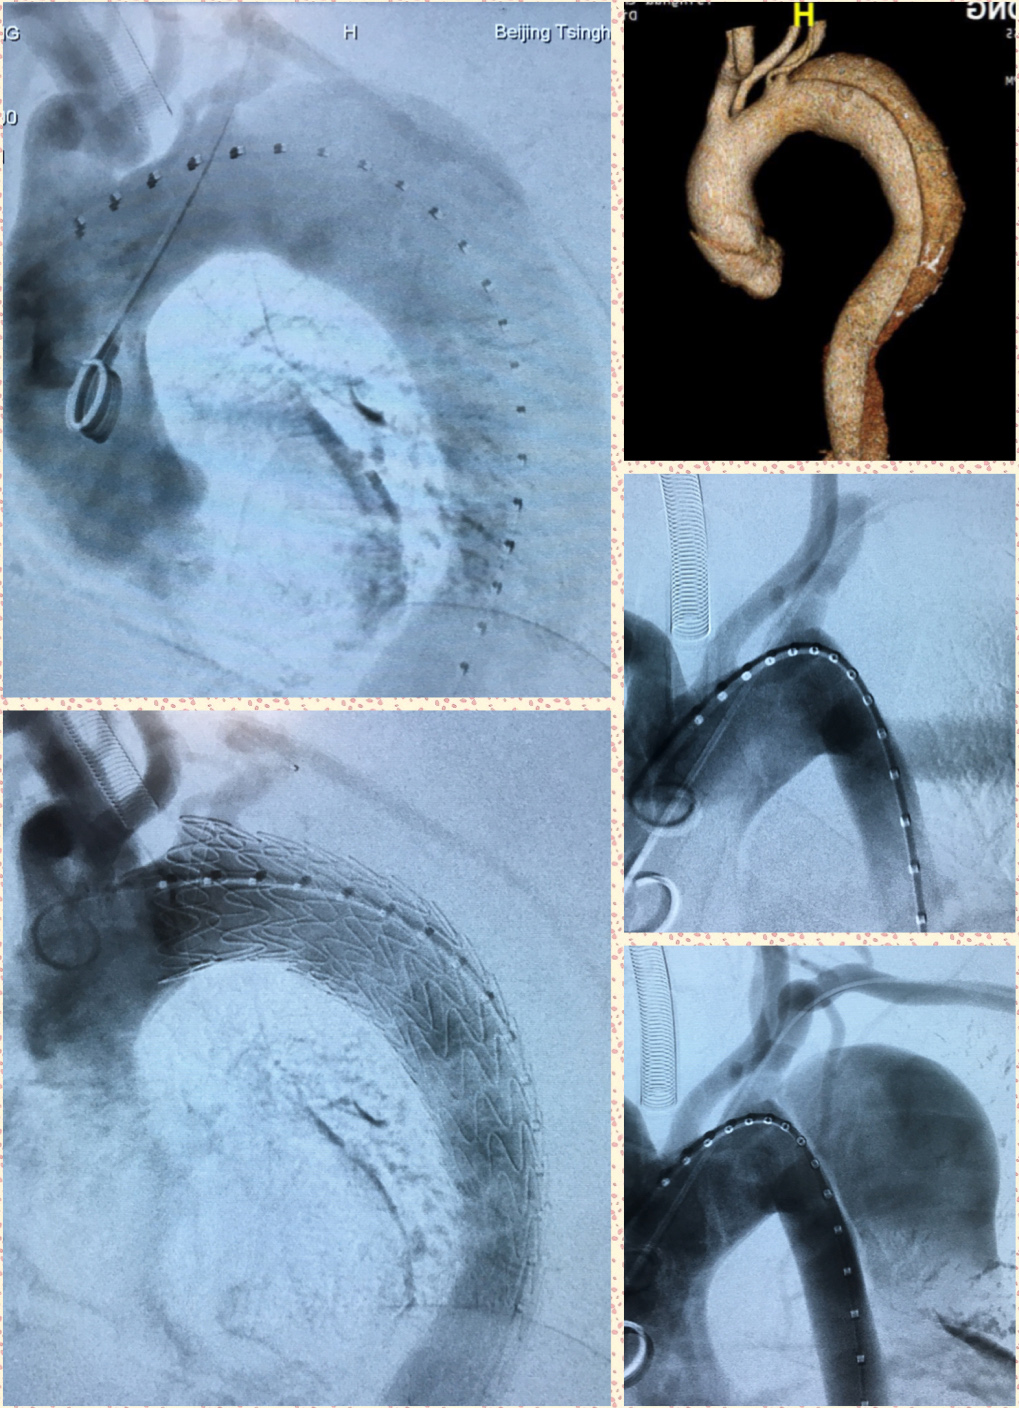

清华长庚医院7月11日电(通讯员 曹战江)近日,北京清华长庚医院血管外科成功完成一例胸主动脉夹层腔内修复术,该患者于7月10日康复出院。

接受手术的是位50岁男性患者,原本因阻塞性睡眠呼吸暂停低通气综合征(OSAHS,鼾症)就诊于耳鼻咽喉头颈外科。进行全面健康检查时,经胸主动脉及腹主动脉CT血管成像(CTA)检查,提示主动脉夹层内膜破裂,夹层累及范围自左侧锁骨下动脉以远至左侧髂总动脉。耳鼻喉科立即联系转诊患者至血管外科。在麻醉科、手术室的配合下,血管外科吴巍巍主任带领团队,成功为该患者实施微创的胸主动脉夹层腔内修复术,术后效果良好。

图为主动脉夹层腔内修复术中影像